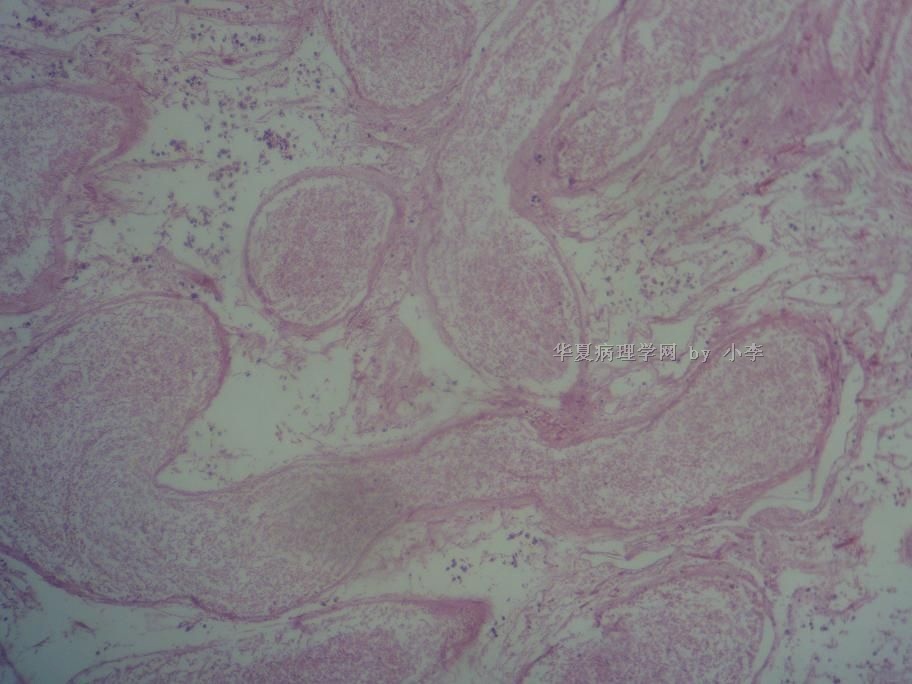

睾丸炎?

姓    名: ××× 性别:  男 年龄: 46岁

• 睾丸炎?图4

图4

首先考虑精子肉芽肿

慢性肉芽肿性炎

肉芽肿性睾丸炎

精子肉芽肿